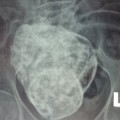

bào thai đá

“Bào thai đá” trong bụng bà cụ 76 tuổi

Kết quả chụp X-quang cho thấy, có bào thai nằm trong ổ bụng một cụ bà nhiều năm. Trưa 24/3, bác sĩ Lê Quang Vinh, Phó giám đốc Bệnh viện Đa khoa khu vực Cam Ranh, cho biết, vừa